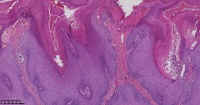

脂溢性角化症?

性别

女

年龄

61岁

一般病史

背部皮肤包块

标本名称

图2

脂溢性角化病